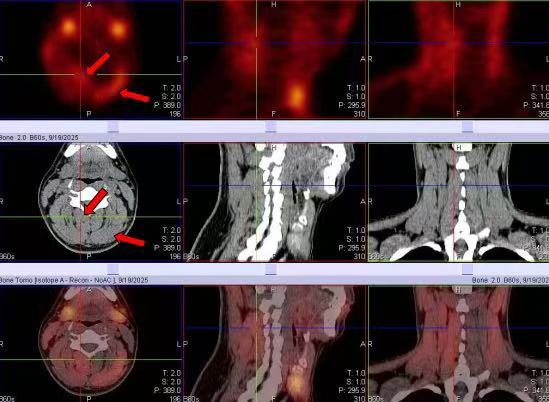

患者的右侧胸锁乳突肌、右侧颈棘肌、左侧头夹肌等肌肉的显像剂摄取明显增高(红箭头)。